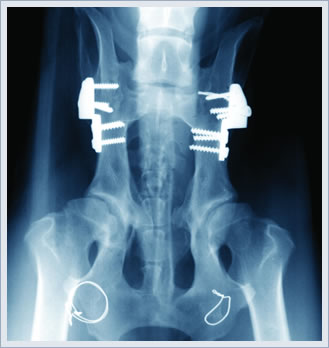

Teşhisin konulmasında hastalığın geçmişi ile el ve ayakların röntgen filmleri belirleyici olmaktadır. Laboratuar değerleri sadece fikir vermektedir. Hastalığın sebep olacağı zararları engellemek veya geciktirmek için uygun tedavinin vakit geçirilmeden başlaması önemlidir. Bu tedavi, temel ilaçlar dediğimiz ilaçlarla (özellikle Methotrexat) ve gerekirse iltihap önleyici başka ilaçların kombinasyonu ile yapılmaktadır. Tamamlayıcı olarak fizik tedavi, Ergoterapi, Hasta jimnastiği ve cerrahi tedavi yardımcı olmaktadır.

Teşhisin konulmasında hastalığın geçmişi ile el ve ayakların röntgen filmleri belirleyici olmaktadır. Laboratuar değerleri sadece fikir vermektedir. Hastalığın sebep olacağı zararları engellemek veya geciktirmek için uygun tedavinin vakit geçirilmeden başlaması önemlidir. Bu tedavi, temel ilaçlar dediğimiz ilaçlarla (özellikle Methotrexat) ve gerekirse iltihap önleyici başka ilaçların kombinasyonu ile yapılmaktadır. Tamamlayıcı olarak fizik tedavi, Ergoterapi, Hasta jimnastiği ve cerrahi tedavi yardımcı olmaktadır.